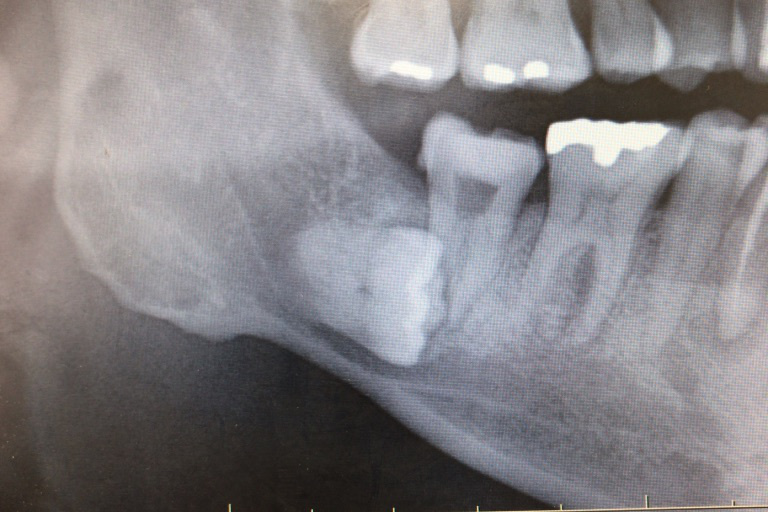

☆☆☆

やや難しい抜歯.15分程度かかりました.この難易度が分かる方,さては口腔外科医ですね.下顎枝が前にあって,道具が入りません.根も膨らんでるし,神経も近いし気を使います.これくらいなら初診日に抜歯します.